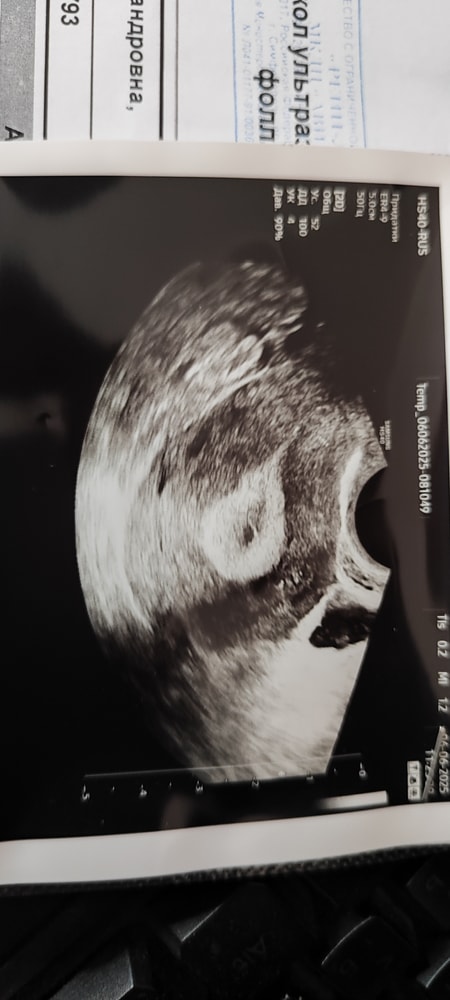

УЗИ после овуляции ,фоликулометрия

УЗИДобрый день. Цикл у меня 30-32 дня. Овуляция по календарю была 1 июня( 18 Дц), на 24 день цикла пошла на фоликулометрию.

Жёлтое тело размером 23 мм, эндометрий 15,7

Врач предположила беременность

И сделала такое фото . Подскажите пожалуйста, у кого так было? Подтвердилась ли беременность? Сейчас 28 дц, вчера не удержалась и сделала тест, одна полоска